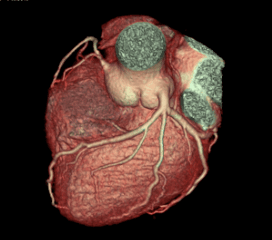

Cardiac CT imaging is a non-invasive diagnostic technique that uses advanced computed tomography technology to create detailed images of the heart and coronary arteries. Our revolutionary CT scanner can capture the entire heart in just one rotation, providing exceptional image quality with minimal radiation exposure.

This advanced imaging technique allows for comprehensive evaluation of cardiac structures, coronary arteries, and heart function, enabling early detection and accurate diagnosis of various heart conditions.

- •3D cardiac reconstruction